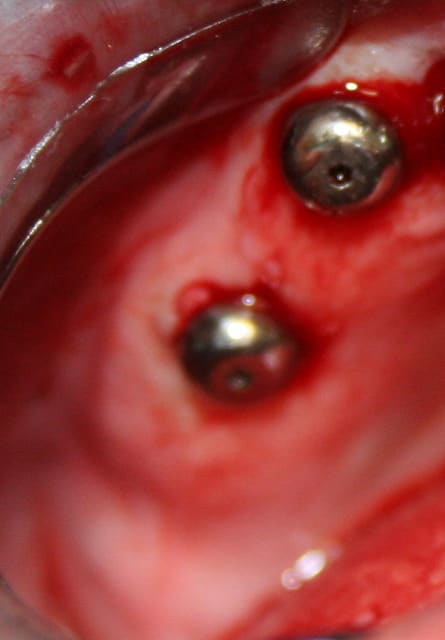

Cas clinique n° 3

posit, le cas 3, avec les deux implants symphysaire, sans doute pour locator, a quand même l'air assez simple a main-levé .

tu as beaucoups de demande pour de petites interventions comme celle-ci ?

J’en ais eu plusieurs pour 2 et 4 implants symphysaire, outre le fait de paralléliser ou avoir une angulation maitrisée la procédure permet un lambeau à minima et une localisation de l’artère sublinguale. Cette intervention peut être parfaitement réalisée à main levée. Lorsqu’ ‘il y a défaut de parallélisme des usures prématurées des Locator peuvent être constatées. Une chirurgie à main levée à un coût plus économique qu’une chirurgie guidée le choix peut se faire aussi en thermes de sécurité, confort, résultat,…